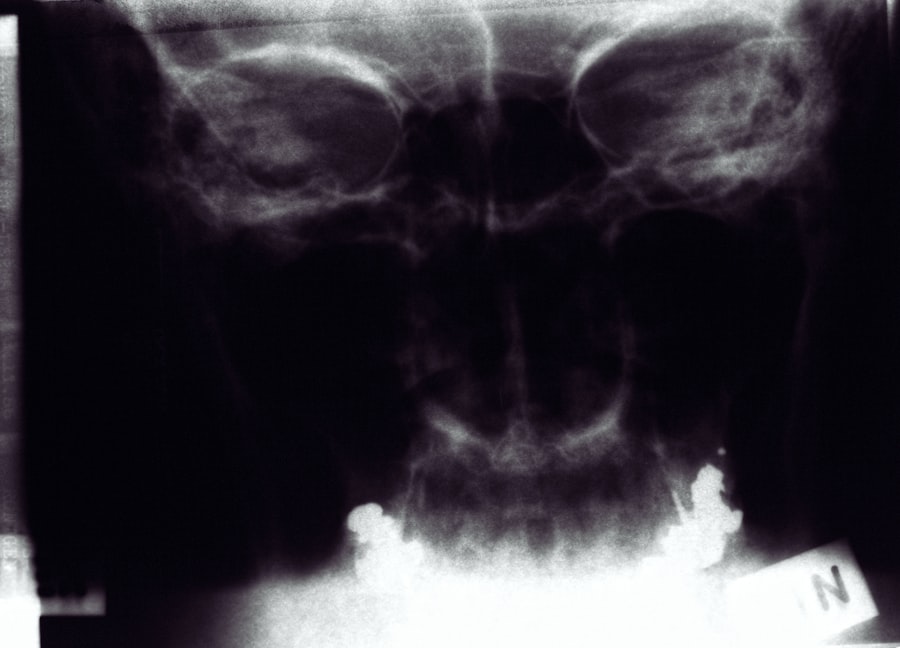

When X-rays pass through the body, they are absorbed at different rates by different tissues. Dense materials like bones absorb more X-rays and appear white on the resulting image, while softer tissues allow more X-rays to pass through and appear darker. This contrast creates a detailed image that can help healthcare professionals identify abnormalities or injuries. The entire process is quick, often taking just a few seconds, making it a convenient option for both patients and medical staff.

X-rays play a pivotal role in diagnosing various diseases and conditions across multiple medical specialties. In orthopedics, they are essential for identifying fractures, dislocations, and degenerative joint diseases like arthritis. By providing clear images of bone structures, X-rays enable orthopedic surgeons to make informed decisions regarding treatment options.

In addition to musculoskeletal issues, X-rays are crucial in detecting diseases affecting internal organs. For example, chest X-rays are commonly used to identify conditions such as pneumonia, heart failure, or lung cancer. By visualizing the lungs and surrounding structures, healthcare providers can assess the severity of these conditions and determine appropriate interventions. This diagnostic capability underscores the importance of X-rays in comprehensive patient care.